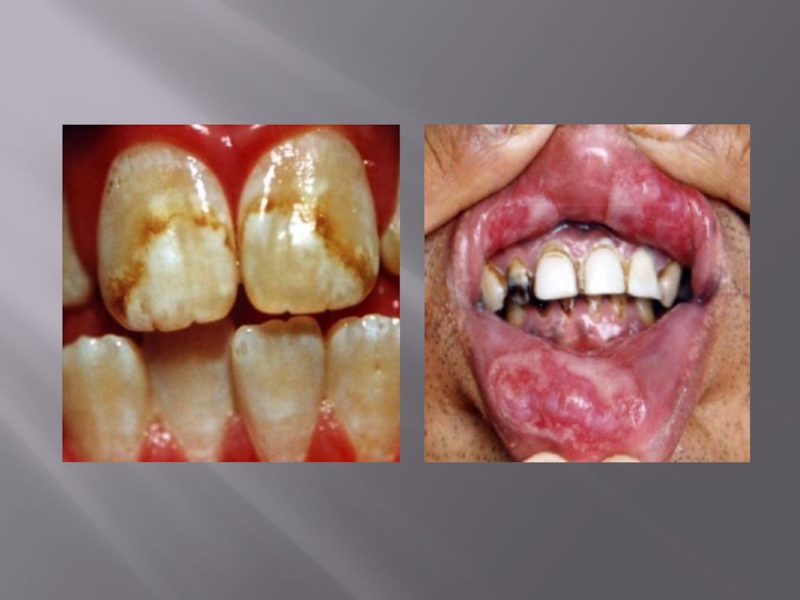

Слайд 31Поздний врождённый сифилис

Наблюдается у детей дошкольного и школьного

возраста, а также взрослых.

Проявления: «триада Гетчинсона» – паренхиматозный

кератит, глухота, деформированные бочкообразные зубы с гипоплазией эмали и образованием выемки на одном или обоих центральных резцах.

В тимусе – полости, заполненные серозной жидкостью с примесью нейтрофилов и лимфоцитов. Полости окружены валом из эпителиоидных клеток и носят название абсцессов Дюбуа.